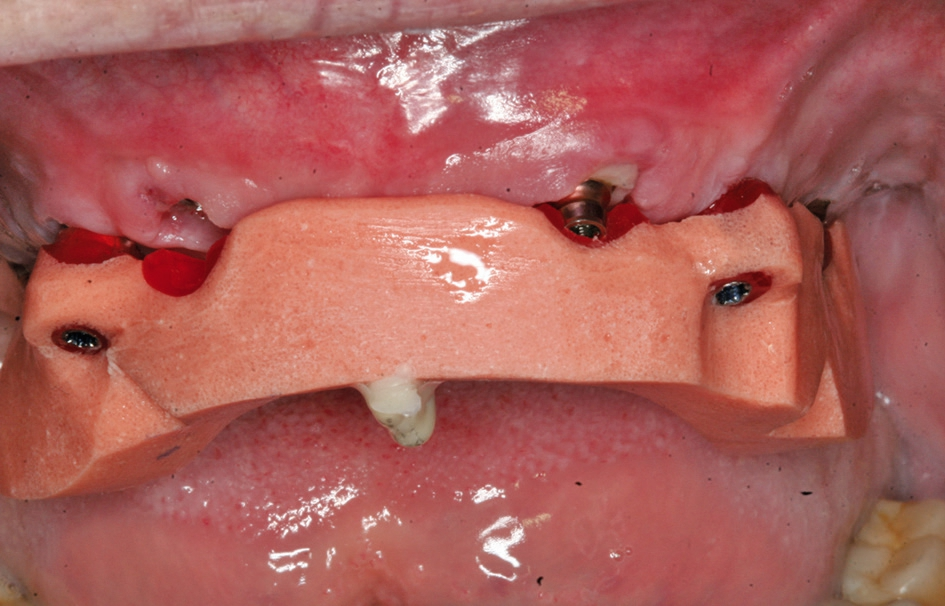

Nach der Freilegung und der Auswahl der angulierten Aufbauten kann die weitere prothetische Versorgung erfolgen. Wenn angulierte Aufbauten nicht nur bei den posterioren Implantaten, sondern auch bei den anderen Implantaten notwendig werden, ist es empfehlenswert, aufgrund der systemimmanenten Restrotation der Sekundärteile, auf ein Auswechseln der Komponenten im Rahmen der prothetischen Versorgung zu verzichten Dies zeigt ferner den Vorteil, dass Mikrobewegungen am Übergang Aufbau Knochenniveau vermieden werden, was zu einer Stabilisierung des Knochenniveaus im Sinne des One-Time-Abutments führen soll [4, 11].

Nach einer initialen Abformung können vom Zahntechniker die optimalen Aufbauten nach der physiologischen Aufstellung und Wachseinprobe ausgewählt werden (Abb. 7 bis 9). Diese werden dann in die Implantate eingeschraubt und verbleiben dort, ohne dass sie wieder entnommen werden. Durch die Auswahl der Aufbauten vom Zahntechniker kann dort auch gleich eine Verblockung vorbereitet werden, mit der es möglich ist, die endgültig erreichte Position der angulierten Aufbauten direkt in das Labor zu übertragen. Somit stellt das Meistermodell eine identische Kopie der klinischen Situation dar. Dies ist notwendig, damit im Rahmen von CAD/CAM-Verfahren Gerüste für die weitere prothetische Versorgung gefräst werden [14]. Je nach Umsetzung der patientenindividuellen Aufstellung kann die definitive Versorgung hergestellt werden. Dort bestehen heute die Möglichkeiten der CAD/CAM-Technologien mit einem Titan- oder einem Keramikgerüst zur Verfügung. Sofern sich kein absolut passgenaues Gerüst erreichen lässt, kann dies durch eine Klebebasis kompensiert werden [5]. Dies wird in der Regel bei reinen Zirkonoxidgerüsten erforderlich. Im weiteren Ablauf kann die individuelle Charakterisierung der Vestibulärflächen und des Weichgewebsübergang erreicht werden (Abb. 10 bis 14).